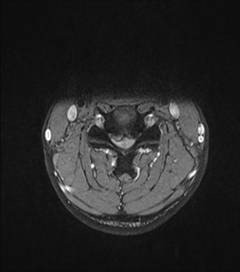

中年男性41歲,因“行走不便2年,加重伴雙手麻木2周”之主訴入院,癥狀主要為:頸部疼痛、僵硬,雙下肢無力、行走不穩(wěn),雙手麻木,協(xié)調性差,右手握筆困難。入院查體:步態(tài)不穩(wěn),C3-C7壓痛、叩擊痛,肢痛溫覺減退,雙上肢肢肌力5-級,雙下肢肌力4-級,肌張力增高,雙下肢腱反射亢進,病理征(+),行頸前路小切口突出椎間盤切除、前路頸椎橋形鎖定植骨融合(ROI-C假體),無需前路鋼板,術后四肢麻木明顯緩解,右上肢精細動作明確增強,可寫字,行走不穩(wěn)消失,肌力基本正常,頸部活動度無明顯受限。(圖1、圖2)

圖1:術前頸椎MRI提示頸椎退行性變,C4/5椎間盤突出、脊髓出現(xiàn)高信號改變,C4硬膜囊受壓變形。